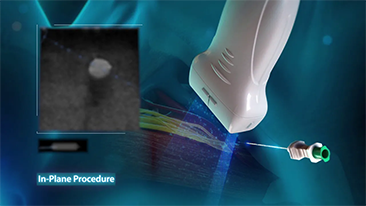

COVID-19: un tiempo desafiante para las personas y los dispositivos

Como consecuencia de la COVID-19, los hospitales y el personal mĂ©dico han desarrollado nuevas prĂĄcticas de trabajo que implican, en los entornos crĂticos, el distanciamiento social, el uso estricto de equipos de protecciĂłn personal (EPP), el lavado de manos y la desinfecciĂłn del equipo todos los dĂas. Los equipos portĂĄtiles altamente mĂłviles y versĂĄtiles pasaron a primer plano en los puntos de atenciĂłn (POC), especialmente cuando las salas y los quirĂłfanos estĂĄn distribuidos en varias plantas y el acceso a los dispositivos especializados es un bien escaso.